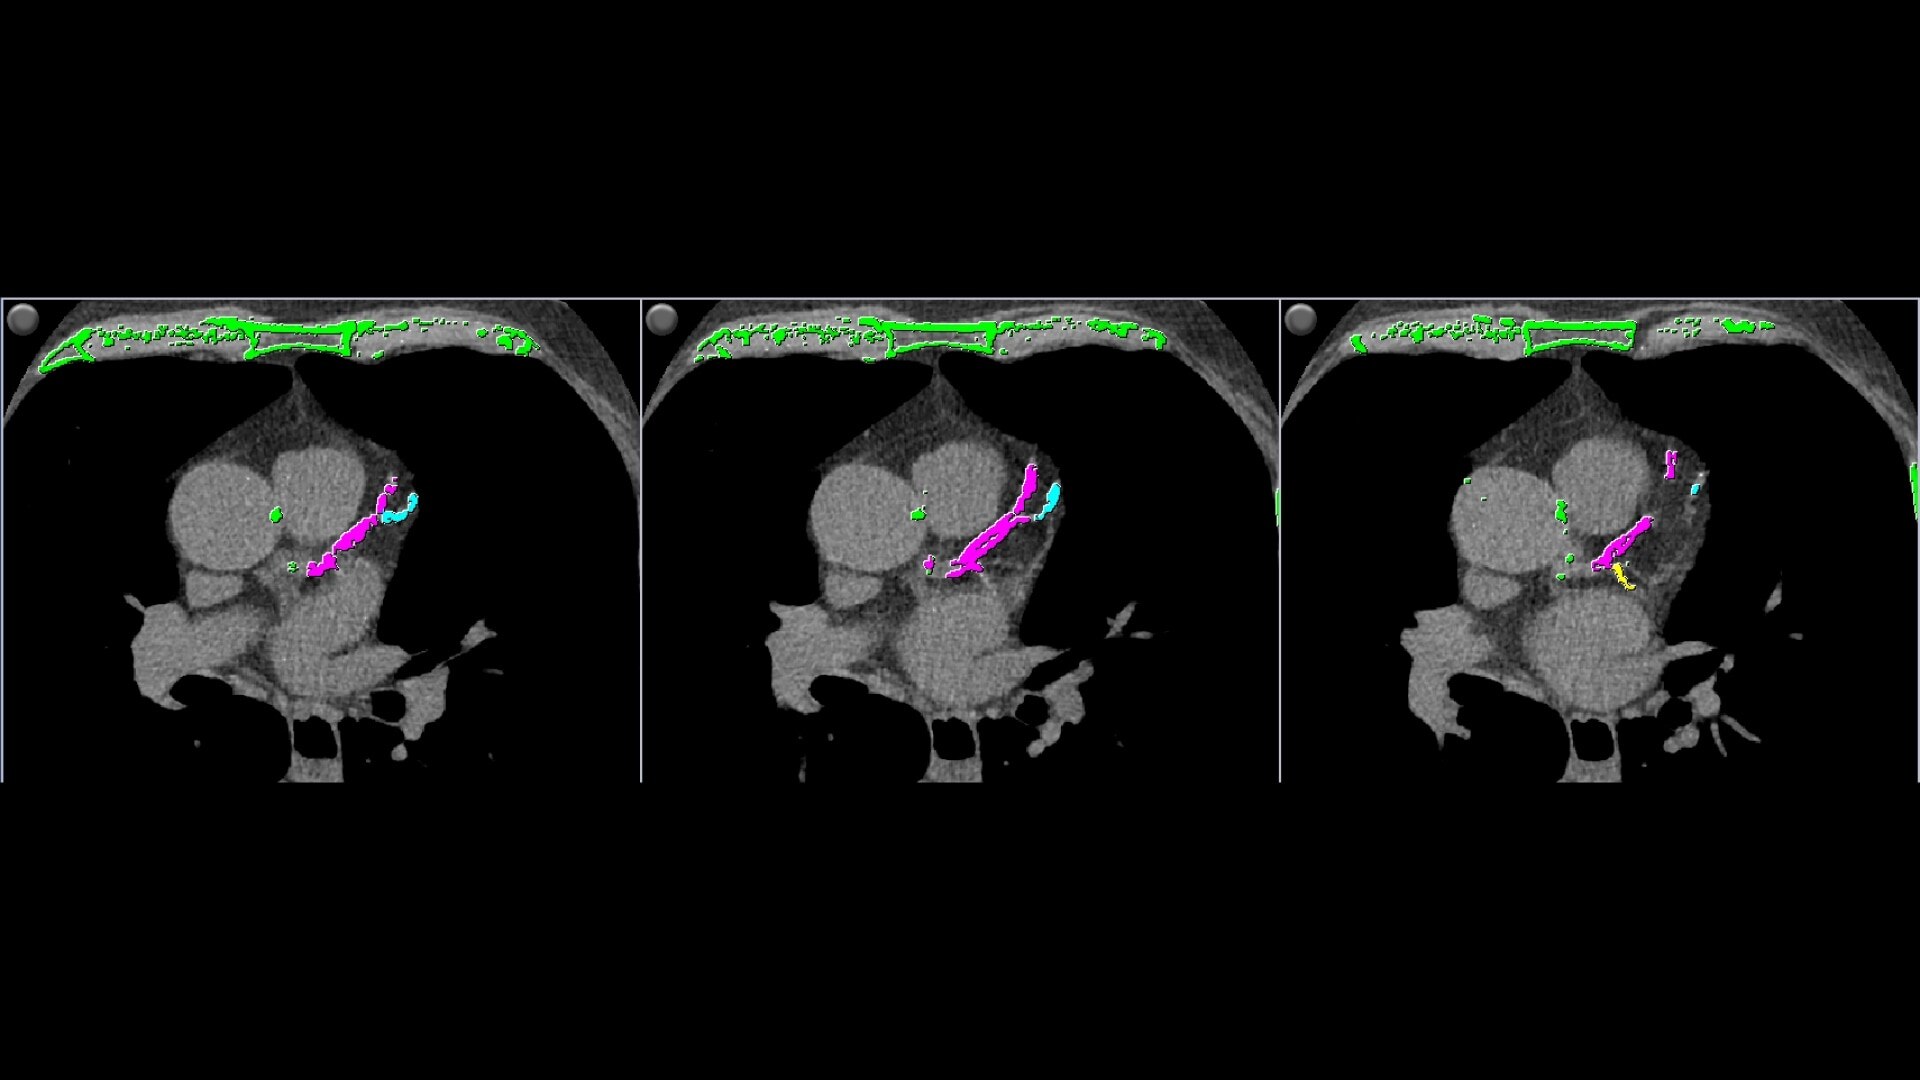

Single-click calcium labeling.

• Individual and aggregate scores are computed for each artery type

• Provides two methods of calcium scoring